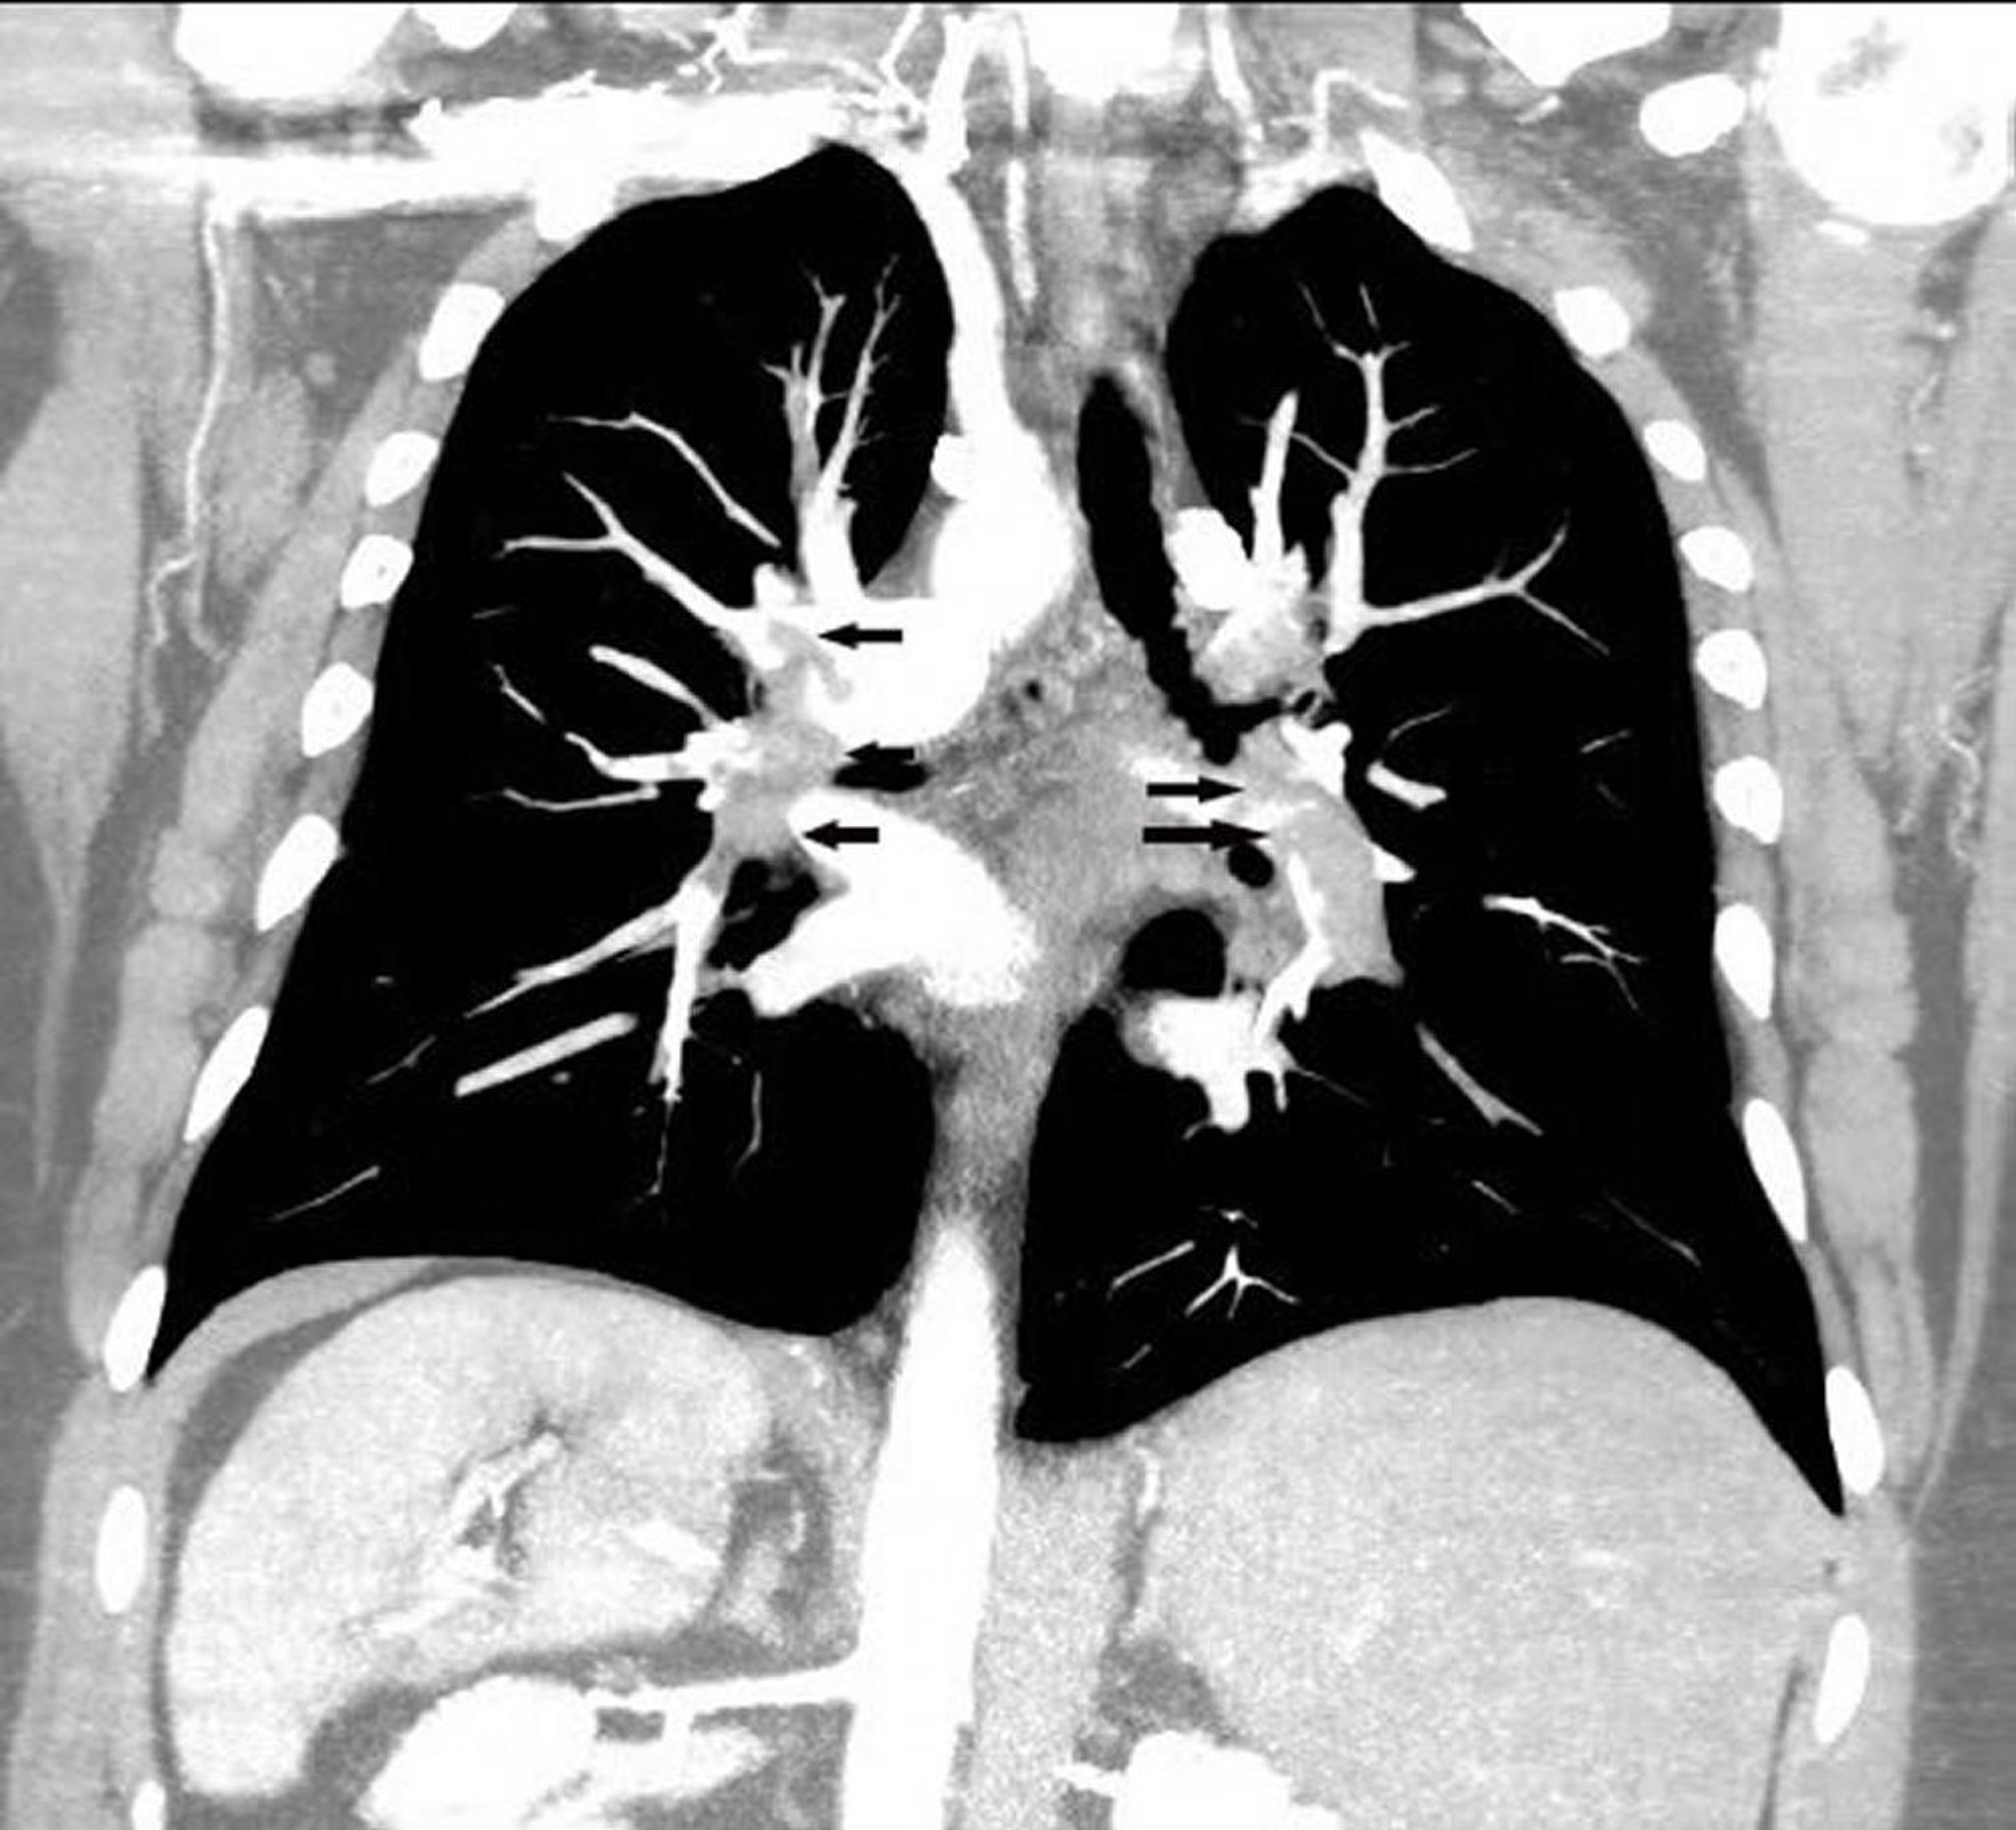

Фронтальная реконструкция, полученная при КТ-ангиопульмонографии

Фронтальная реконструкция, выполненная с помощью КТ-ангиопульмонографии, показывает обширную легочную эмболию в обеих легочных артериях (стрелки).

Image courtesy of Hakan Ilaslan, MD.